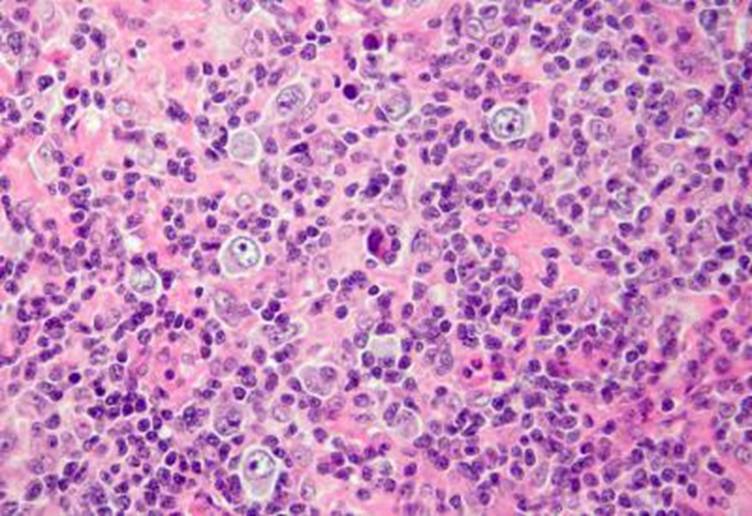

NK buňky

NK buňky.